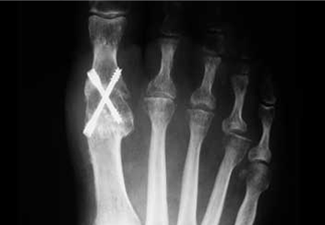

Osteosíntesis de la osteotomía con tornillo.

Combinación de Hallux Valgus clásico y falángico.

Tratamiento del Hallux Valgus combinado con metatarsalgia central.